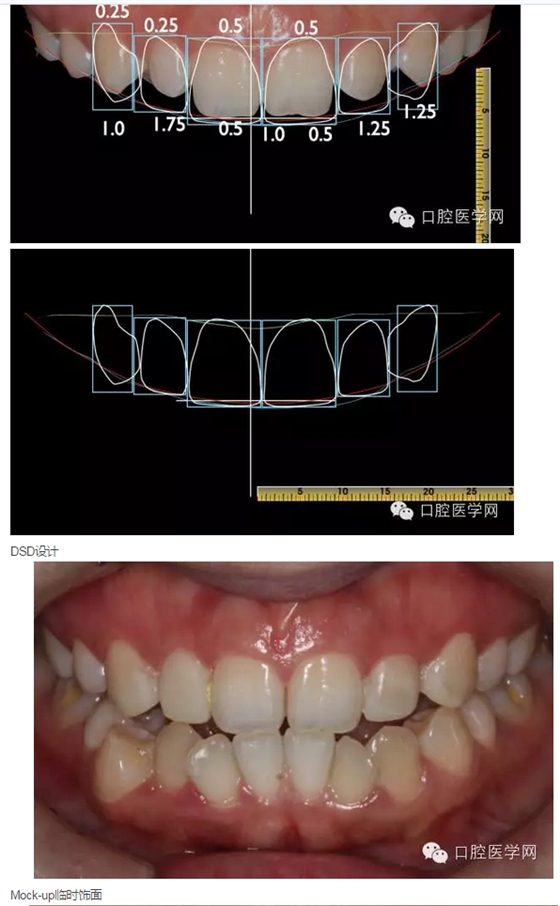

計(jì)劃先拍攝分析照片、制取分析模型,通過(guò)數(shù)字化微笑設(shè)計(jì)(Digital Smile Design)分析患者存在的美學(xué)為題,展示美學(xué)修復(fù)后的大致效果,并指導(dǎo)技師完成美學(xué)蠟形設(shè)計(jì)(Wax-up);再通過(guò)美學(xué)蠟形在口內(nèi)翻制臨時(shí)(DMG)樹脂飾面,讓患者更加直觀的看到美學(xué)修復(fù)后的效果,參與設(shè)計(jì),檢查咬合,在臨時(shí)飾面基礎(chǔ)上進(jìn)行常規(guī)定深備牙,最后根據(jù)共同研究修改后的形態(tài)制取參考模型指導(dǎo)最后的修復(fù),以達(dá)到良好的美學(xué)修復(fù)效果。患者對(duì)原上前牙的顏色尚滿意,故不考慮遮色,選擇更加微創(chuàng)、通透美觀的烤瓷貼面修復(fù)。

2015年3月28日:展示DSD設(shè)計(jì),探討美學(xué)修復(fù)方案(見(jiàn)圖10-15),取模制作美學(xué)蠟形。